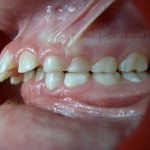

Vue de Droite